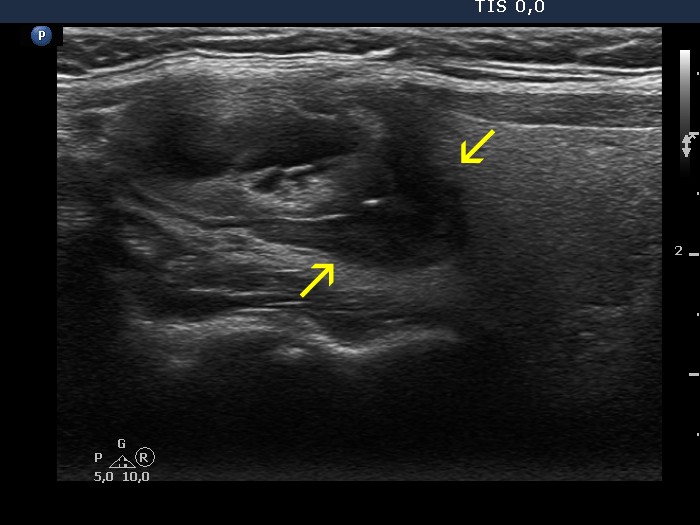

Halo sign and vascular pattern of nodules - case conp 068

Follow-up investigation seven years later (ultrasonographic picture 3b)

Right lobe, longitudinal scan. Note the irregular borders of the lower, deeply hypoechoic nodule.